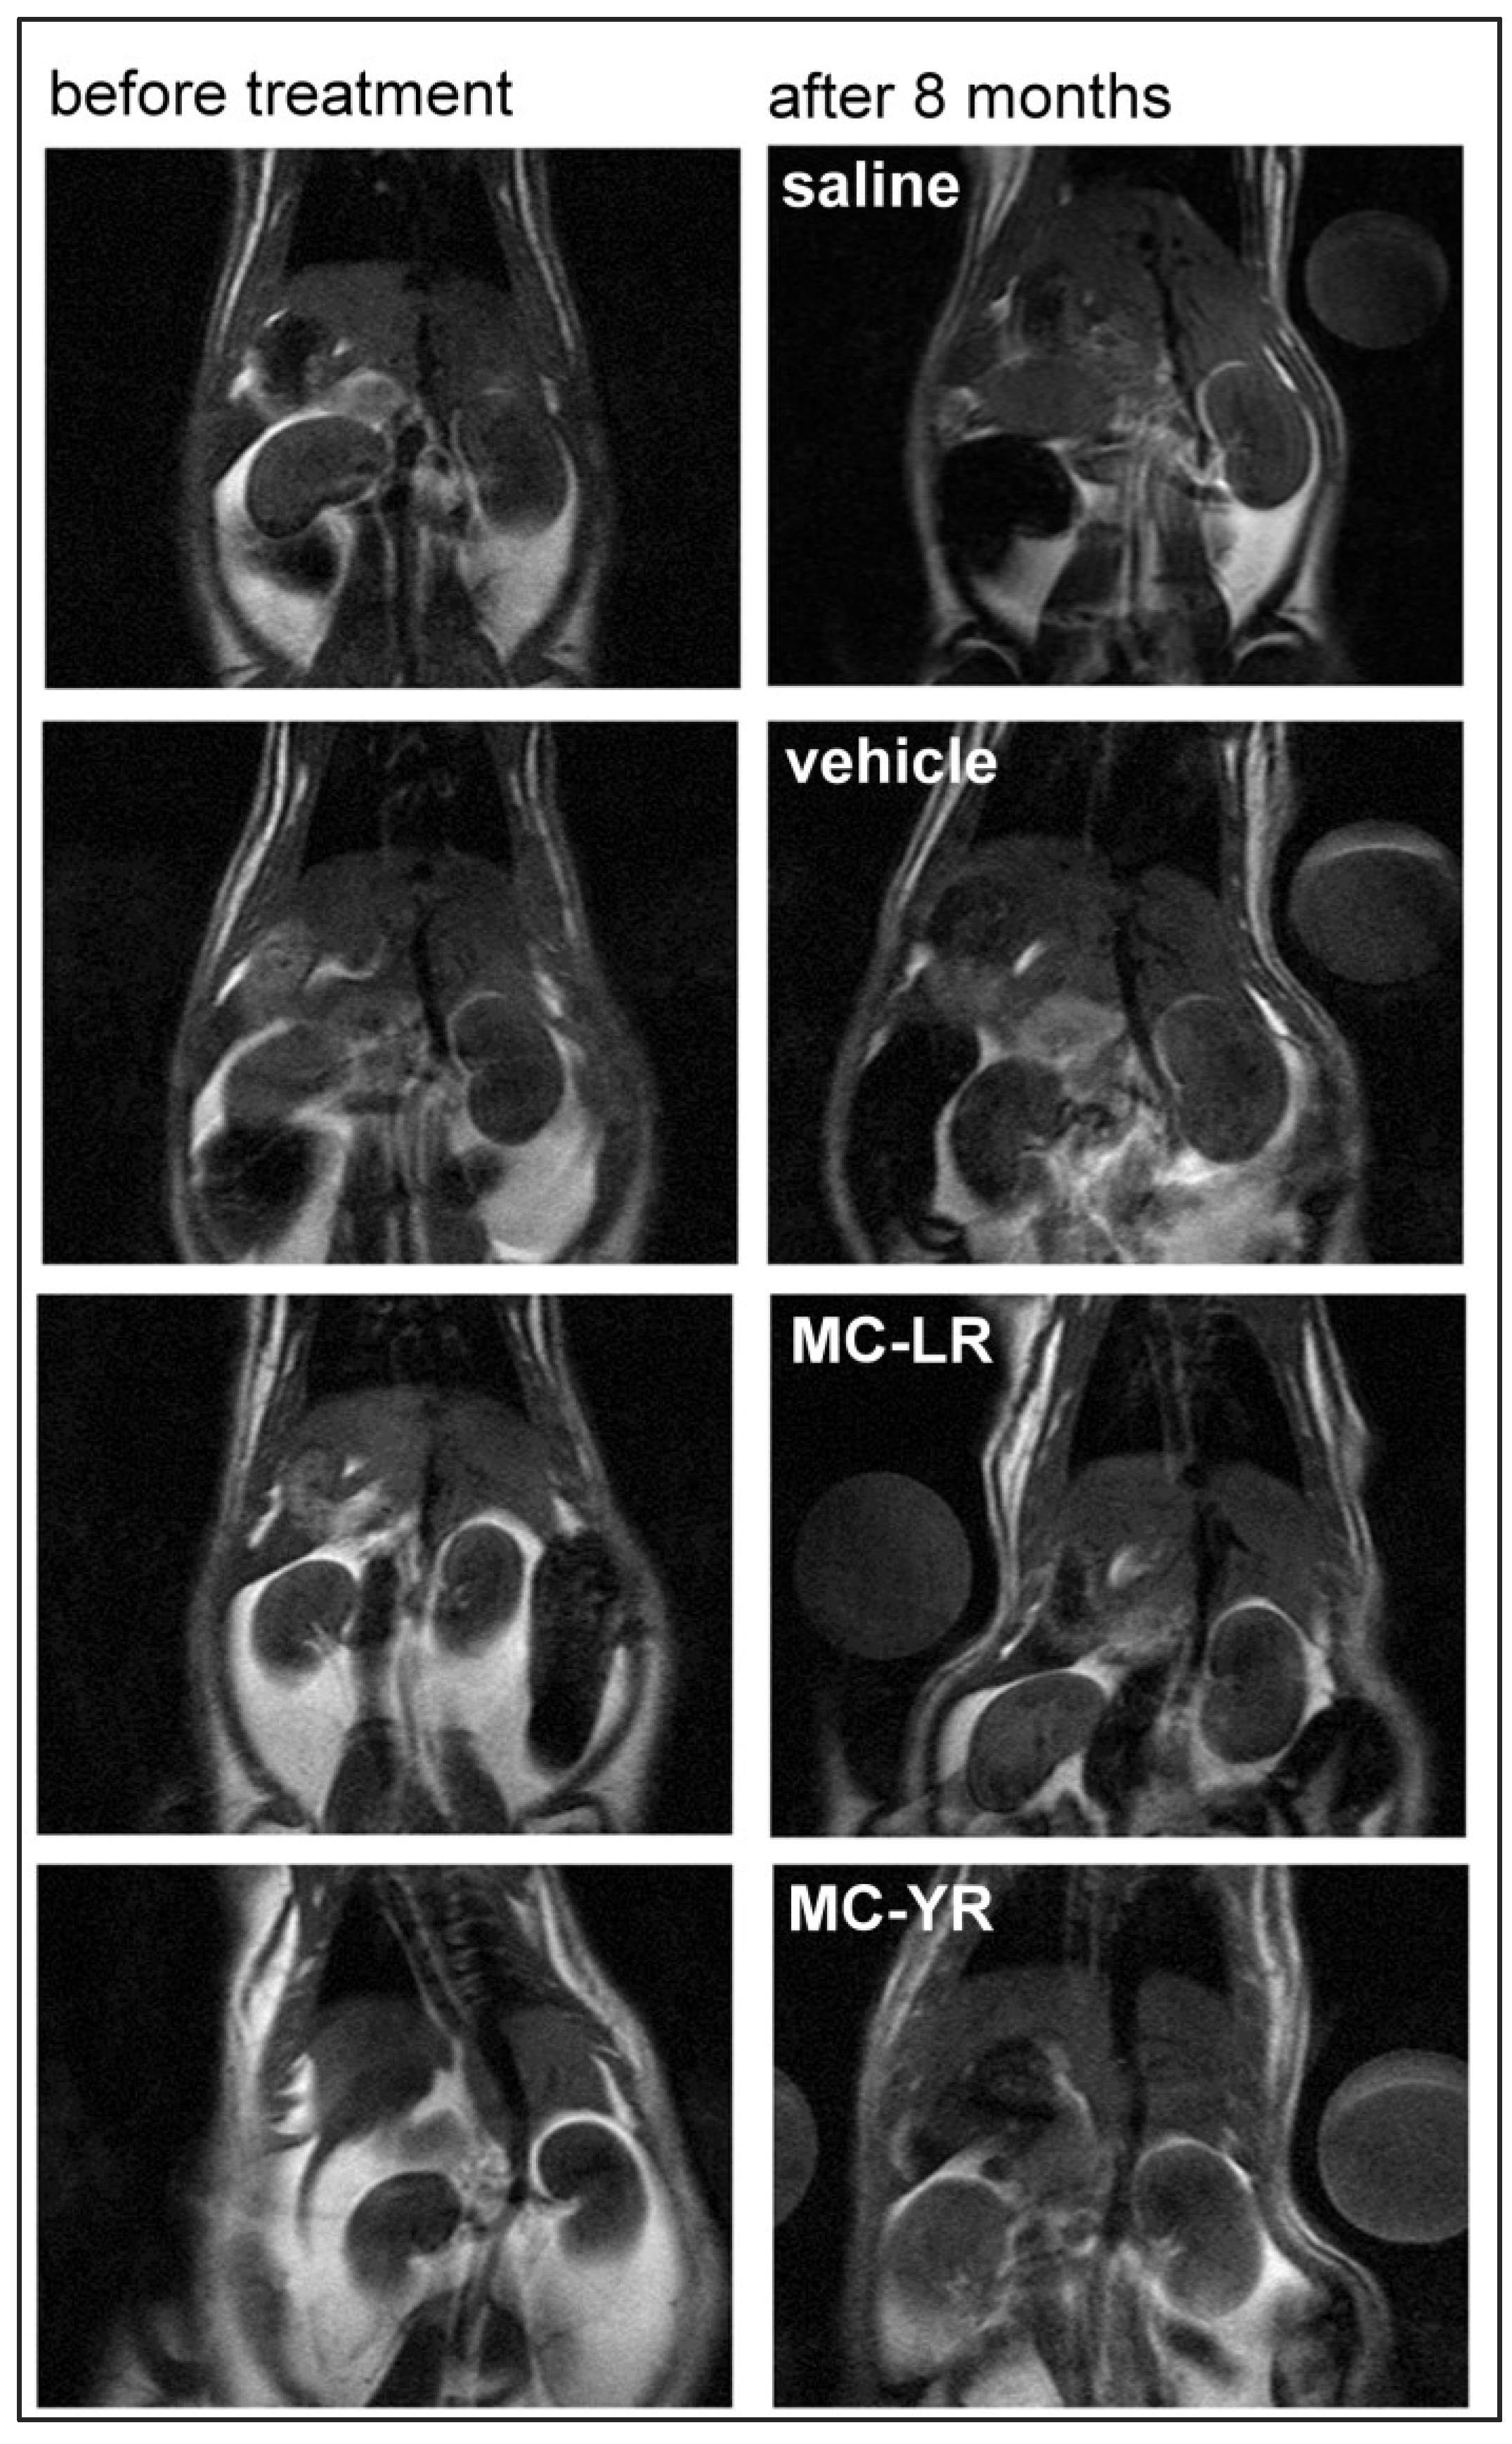

- Milutinovic, A.; Zivin, M.; Zorc-Pleskovic, R.; Sedmak, B.; Suput, D. Nephrotoxic effects of chronic administration of microcystins-LR and -YR. Toxicon 2003, 42, 281–288. [Google Scholar] [CrossRef]

- Frangez, R.; Kosec, M.; Sedmak, B.; Beravs, K.; Demsar, F.; Juntes, P.; Pogacnik, M.; Suput, D. Subchronic liver injuries caused by microcystins. Pflugers Arch. 2000, 440, R103–R104. [Google Scholar] [CrossRef]

- Sturgeon, S.A.; Towner, R.A. In vivo assessment of microcystin-LR-induced hepatotoxicity in the rat using proton nuclear magnetic resonance (1H-NMR) imaging. Biochim. Biophys. Acta 1454, 227–235. [Google Scholar]